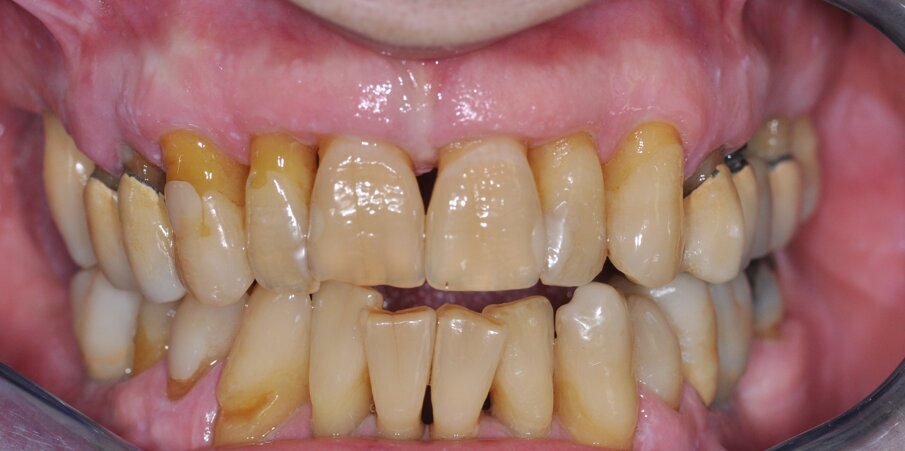

I pazienti considerati eleggibili all’inclusione erano coloro che fossero stati sottoposti a riabilitazione con protesi full-arch a carico immediato con tecnica Flat-one-Bridge (Figg. 1, 2). I pazienti, già al tempo della chirurgia, erano inclusi solo se maggiorenni, complessivamente in salute, condiscendenti alle misure di igiene orale prescritte e alle visite di controllo programmate. I criteri di esclusione erano: presenza di fattori sistemici o locali che avrebbero potuto controindicare la chirurgia, scarsa igiene orale, abitudine al fumo di più di 10 sigarette al giorno, gravidanza, storia di dipendenza e/o abuso di sostanze stupefacenti e/o alcool.

Fig. 1_Foto pre-operatoria di uno dei pazienti inclusi al tempo della chirurgia.